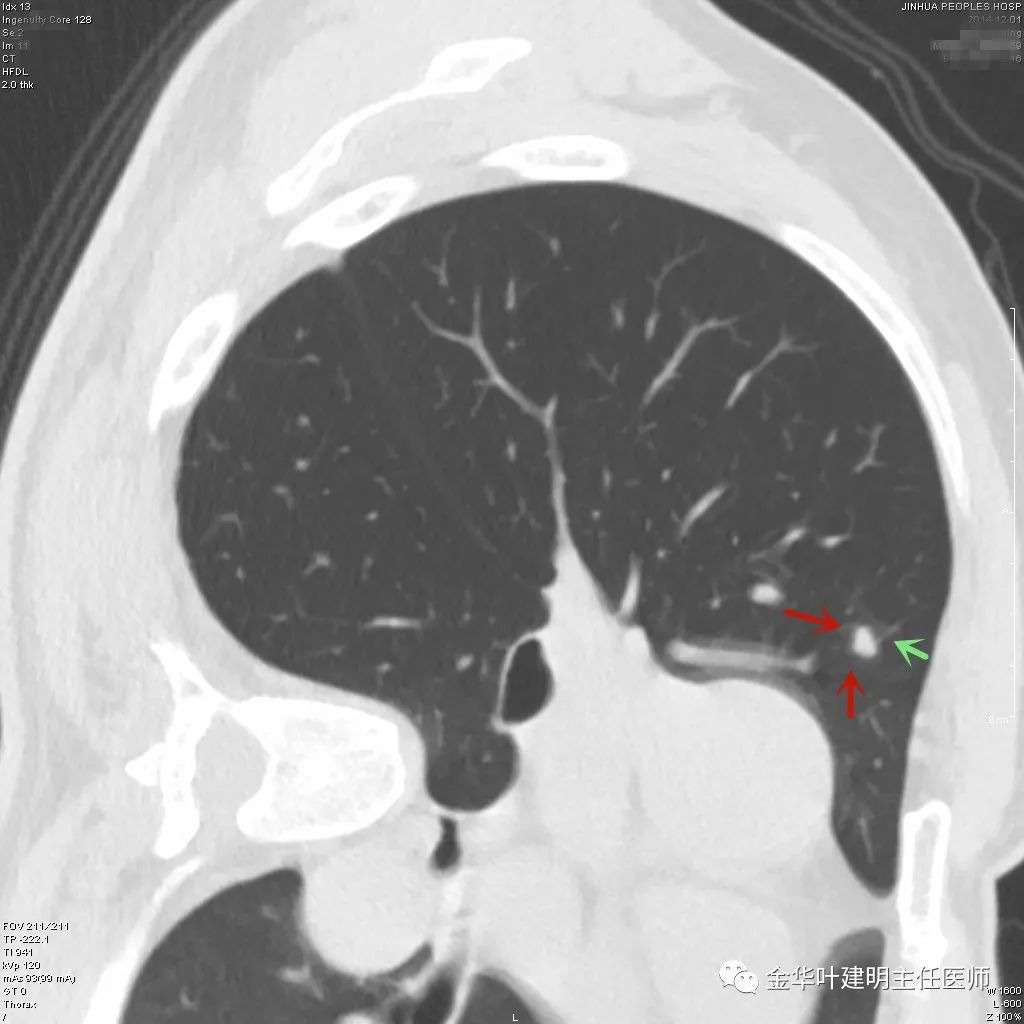

上图示结核。我们发现其有明显的卫星灶,如绿色箭头所示,主病灶处也是周边有模糊区域,病灶整体密度较为均匀(肿瘤容易生长不均致密度欠均匀,显杂乱)。

上图示典型的肺内淋巴结影像。靠近胸膜,高密度,三角形工多边形,相对比较孤立,周围没有炎性渗出或卫星灶,邻近胸膜(包括叶间胸膜)但无胸膜牵拉凹陷。